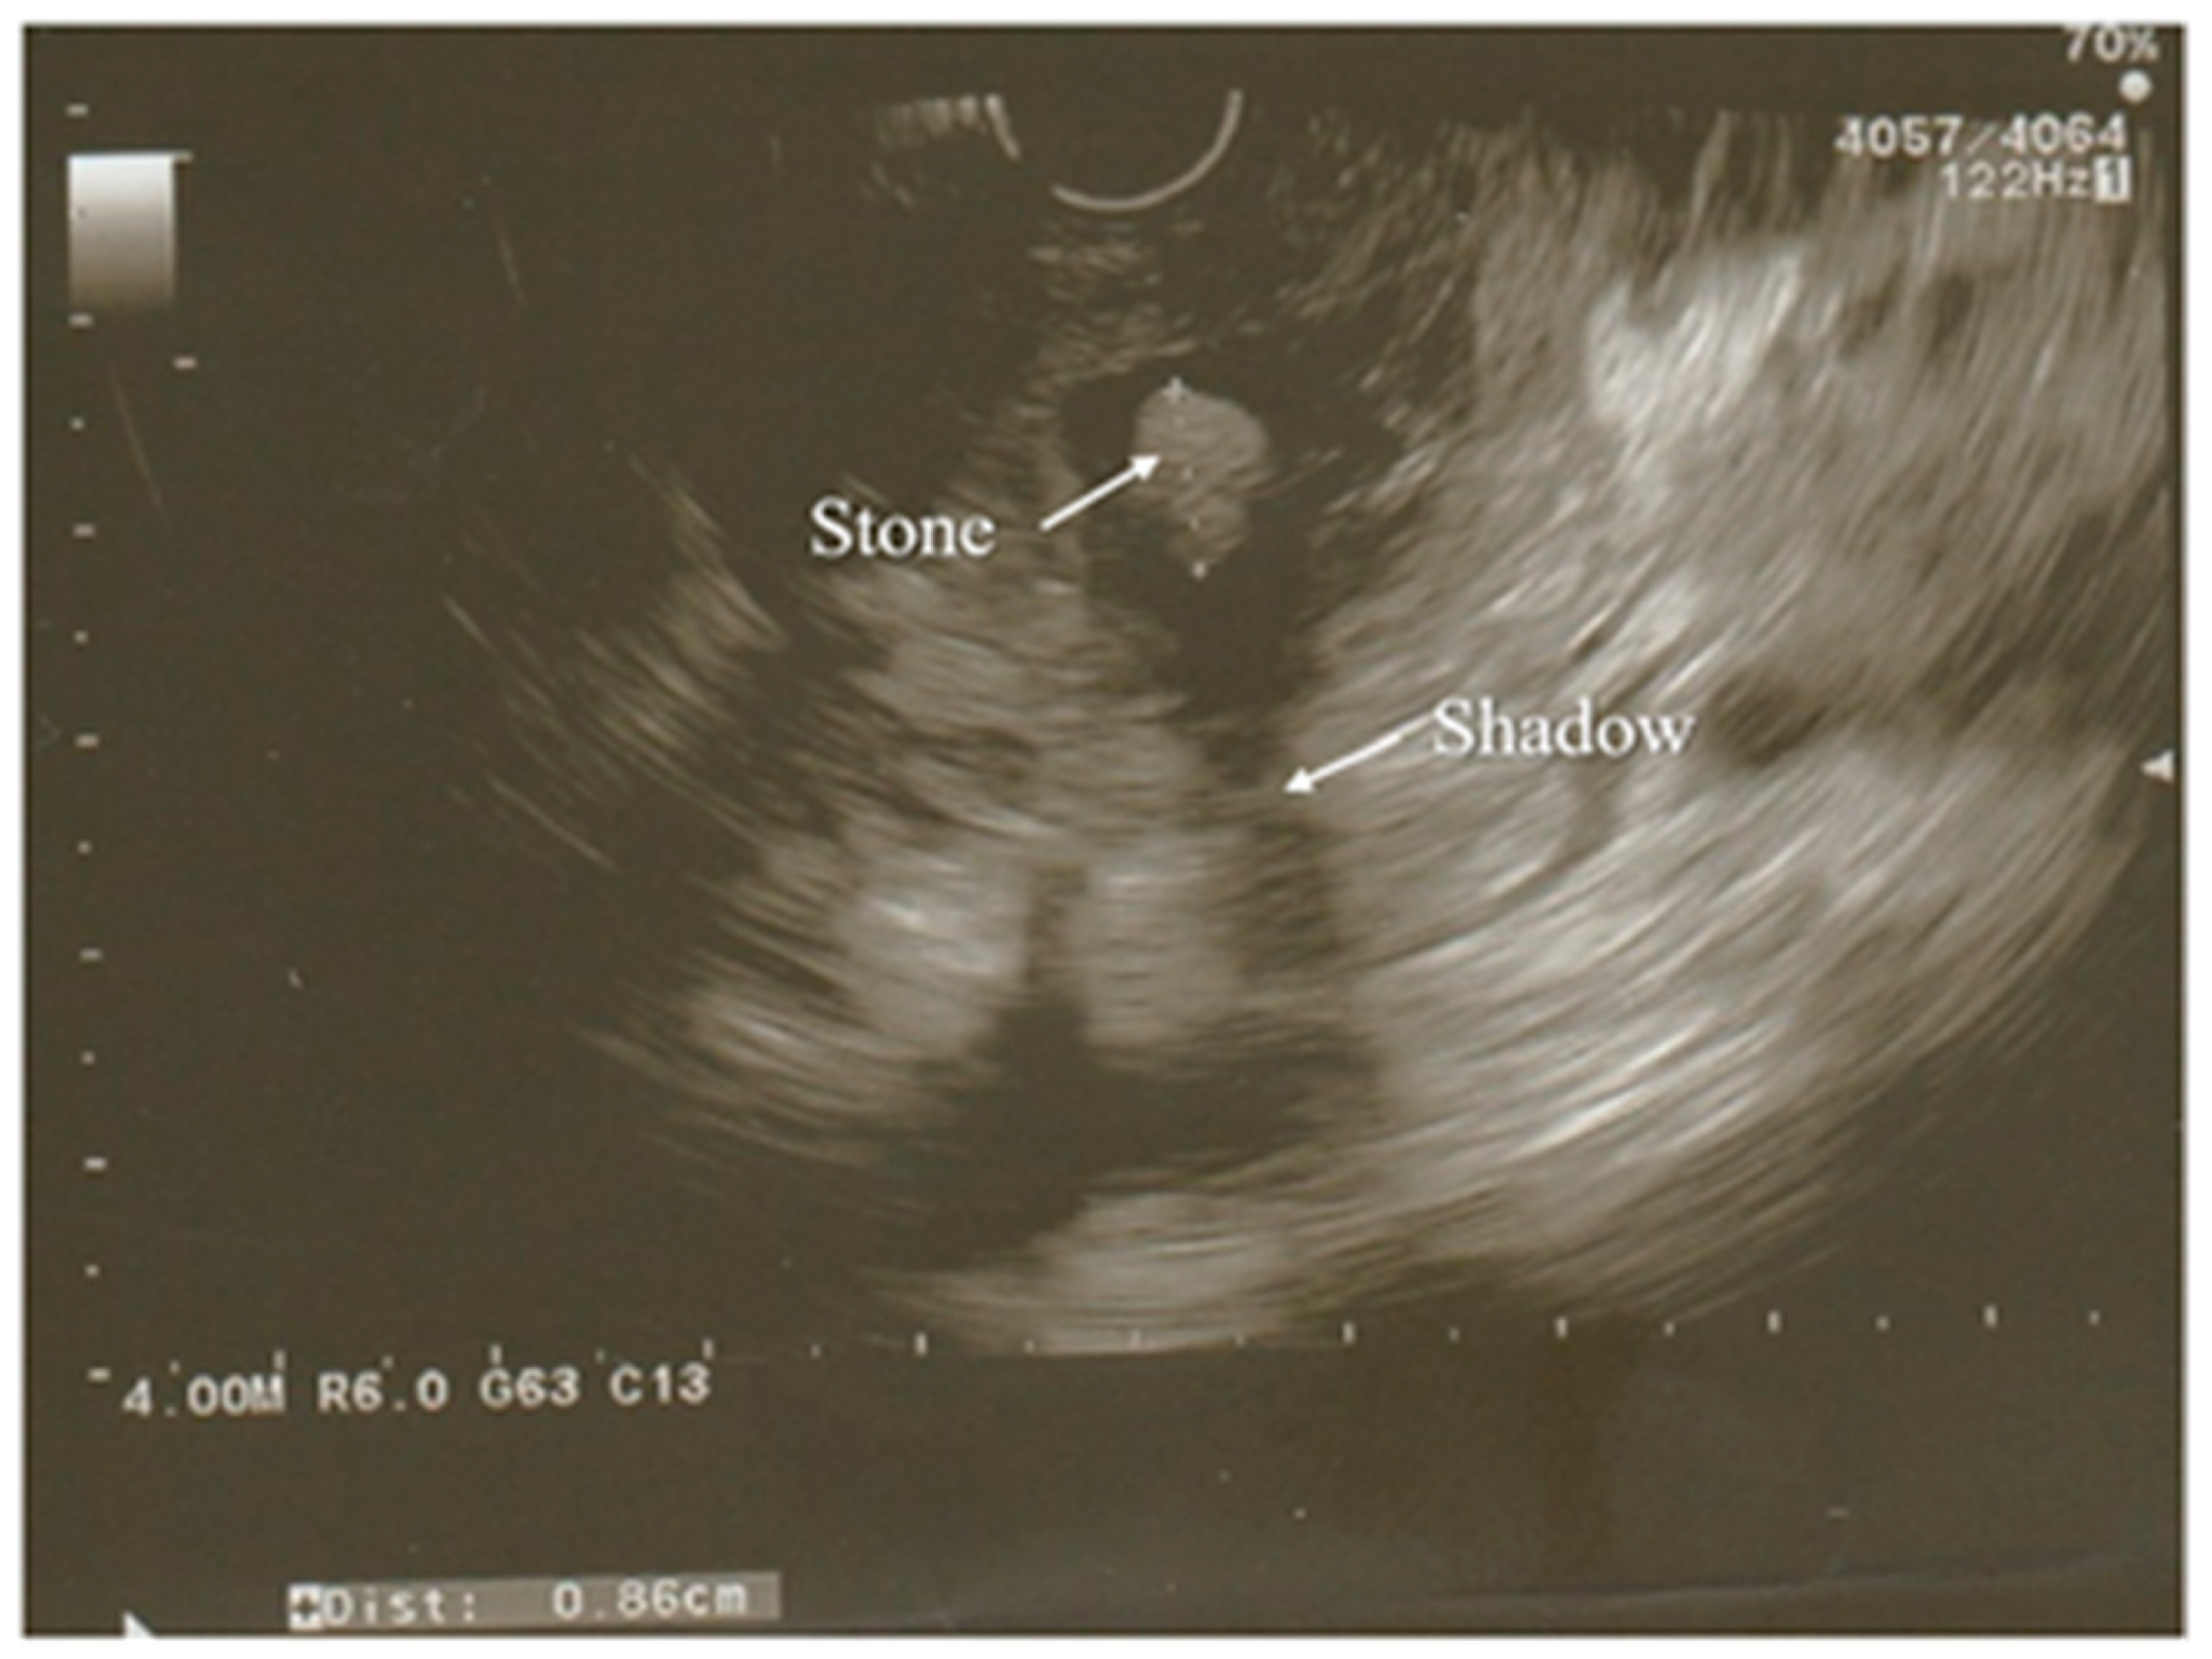

3.3. Ultrasonography

- Liu, C.-L.; Lo, C.-M.; Chan, J.K.-F.; Poon, R.T.-P.; Lam, C.-M.; Fan, S.-T.; Wong, J. Detection of choledocholithiasis by EUS in acute pancreatitis: A prospective evaluation in 100 consecutive patients. Gastrointest. Endosc. 2001, 54, 325–330. [Google Scholar] [CrossRef]

- Rizk, M.K.; Gerke, H. Utility of endoscopic ultrasound in pancreatitis: A review. World J. Gastroenterol. 2007, 13, 6321. [Google Scholar] [CrossRef]

- Kotwal, V.; Talukdar, R.; Levy, M.; Vege, S.S. Role of endoscopic ultrasound during hospitalization for acute pancreatitis. World J. Gastroenterol. 2010, 16, 4888. [Google Scholar] [CrossRef]